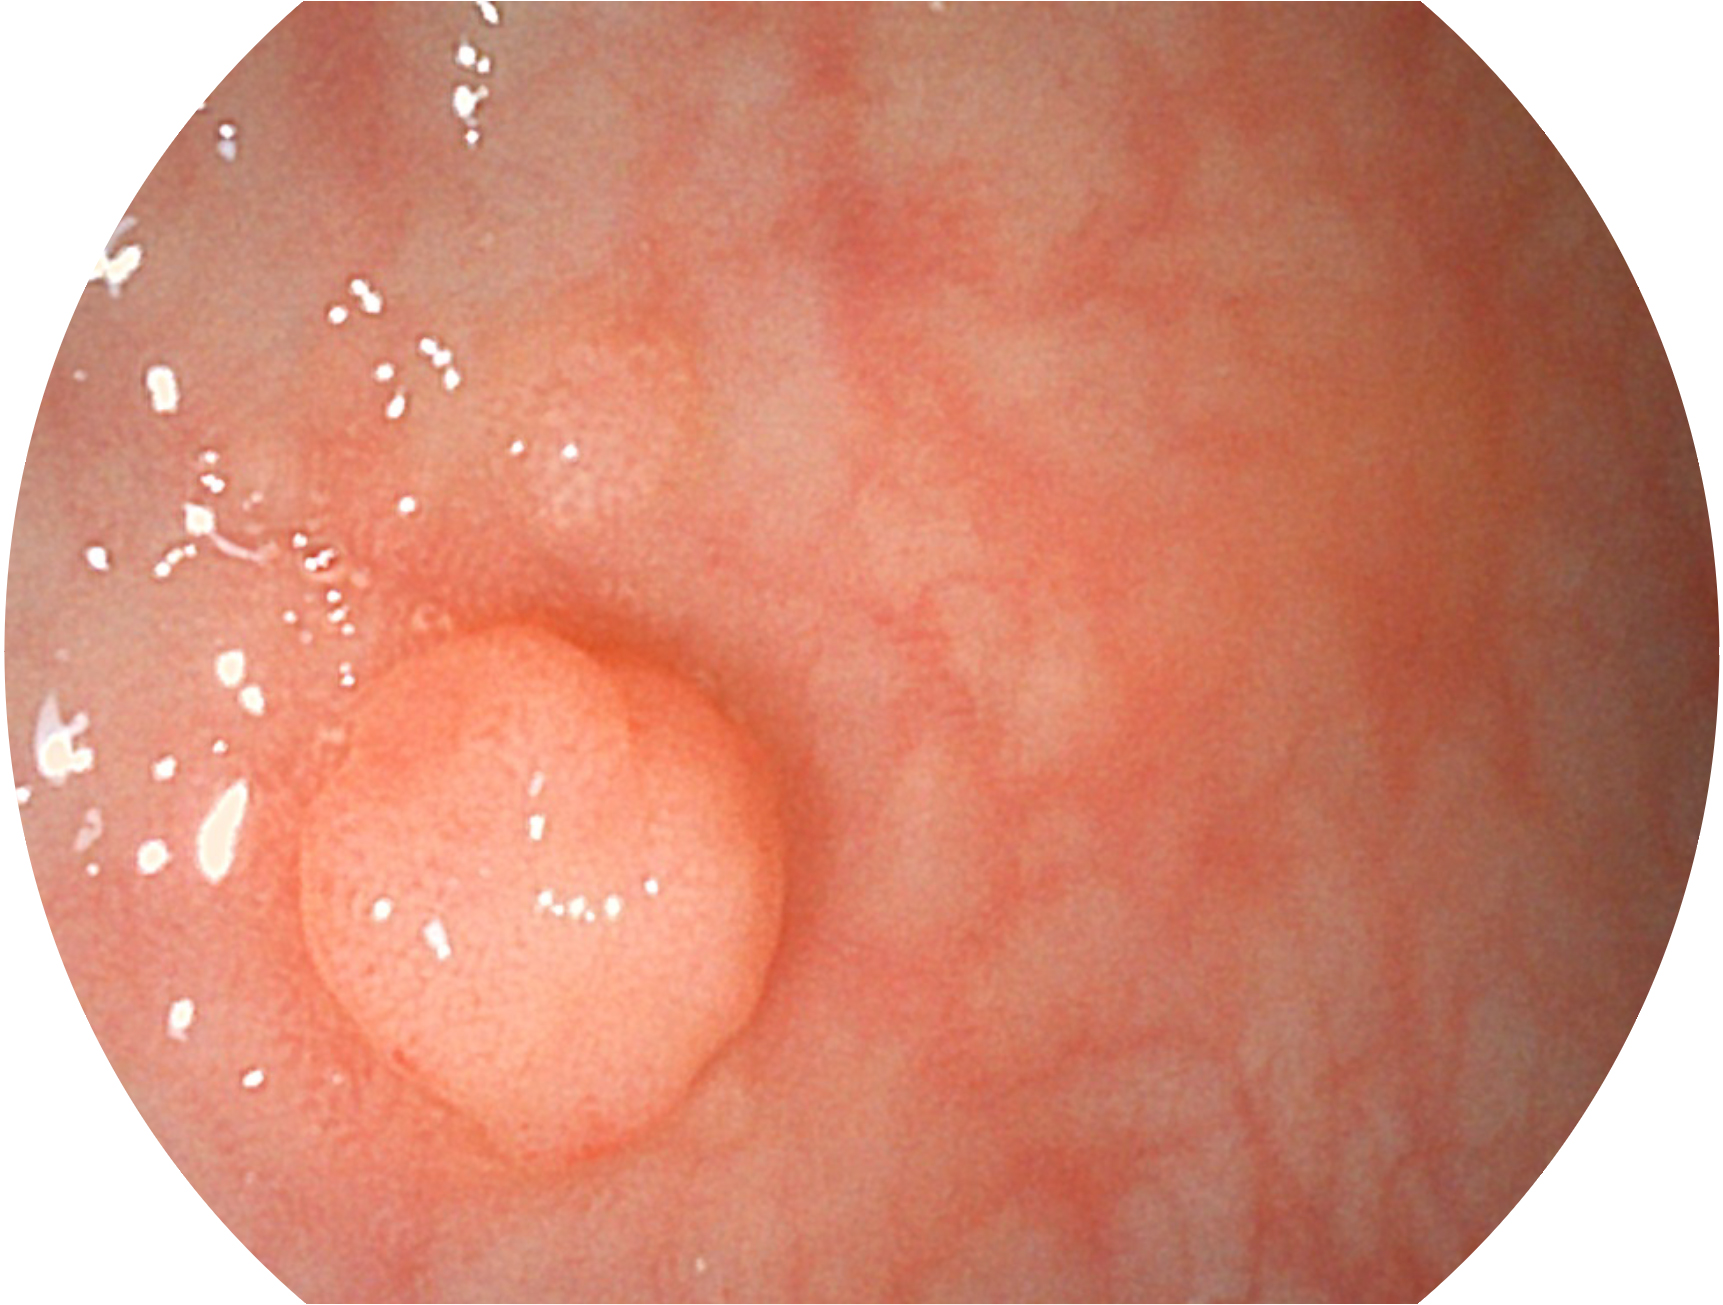

開立新開發(fā)的內(nèi)鏡染色技術(shù),主要是基于多波長(zhǎng)LED 光源的開發(fā),VLS-55Q 四波長(zhǎng)LED 光源是由四個(gè)不同顏色的LED光按照相應(yīng)照明模式所規(guī)定的特定發(fā)光比例進(jìn)行合束后形成,合束后形成的照明光的光譜由紅光、綠光、藍(lán)光及藍(lán)紫光這四個(gè)不同的波段范圍構(gòu)成。具有更高光譜自由度,通過光譜比例的控制,實(shí)現(xiàn)了聚譜成像技術(shù),英文全稱為“Spectral Focused Imaging, SFI”,縮寫為“SFI”和光電復(fù)合染色成像技術(shù),英文全稱為“Versatile Intelligent Staining Technology, VIST”,縮寫為“VIST”。